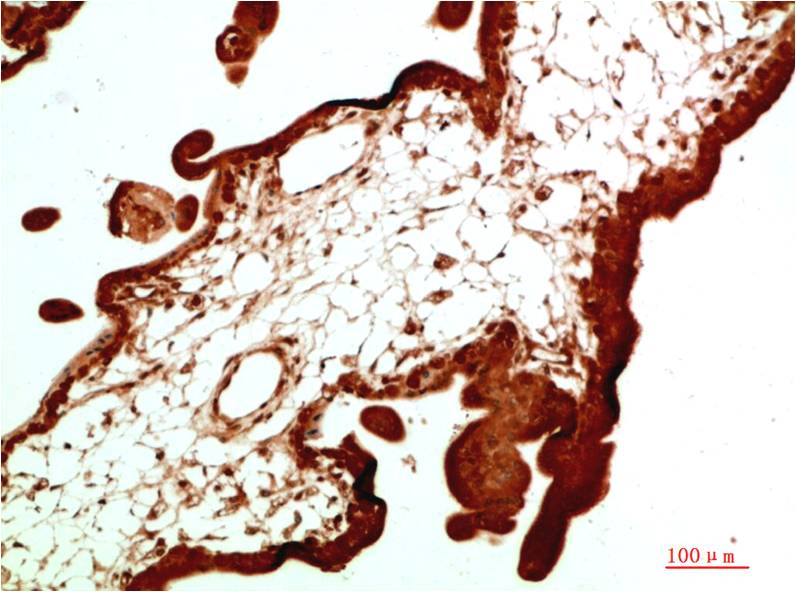

Applications :WB, IHC

| Recommended dilutions: | WB:1:1,000-2,000 IHC:1:200-500 |

| Specificity: | Antibody can detects endogenous STAT1 protein. |